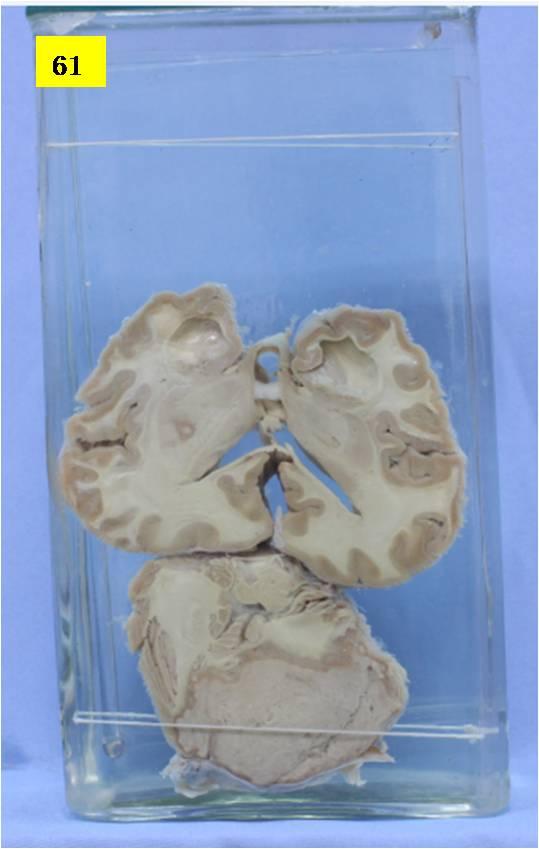

神经疾病-64-61.恶性室管膜瘤(源于第四脑室)

小脑水平切片,见小脑中央被灰白色的肿瘤组织所占据。肿瘤质地较松,有浅表性脱落,肿瘤和正常组织分界不清,其大致量度为4×5cm,并可见灶性出血灶(黑色),并局部转移到基底节,侧脑室、中脑导水管扩张(脑积水),经镜下证实为室管膜瘤(源于第四脑室)。